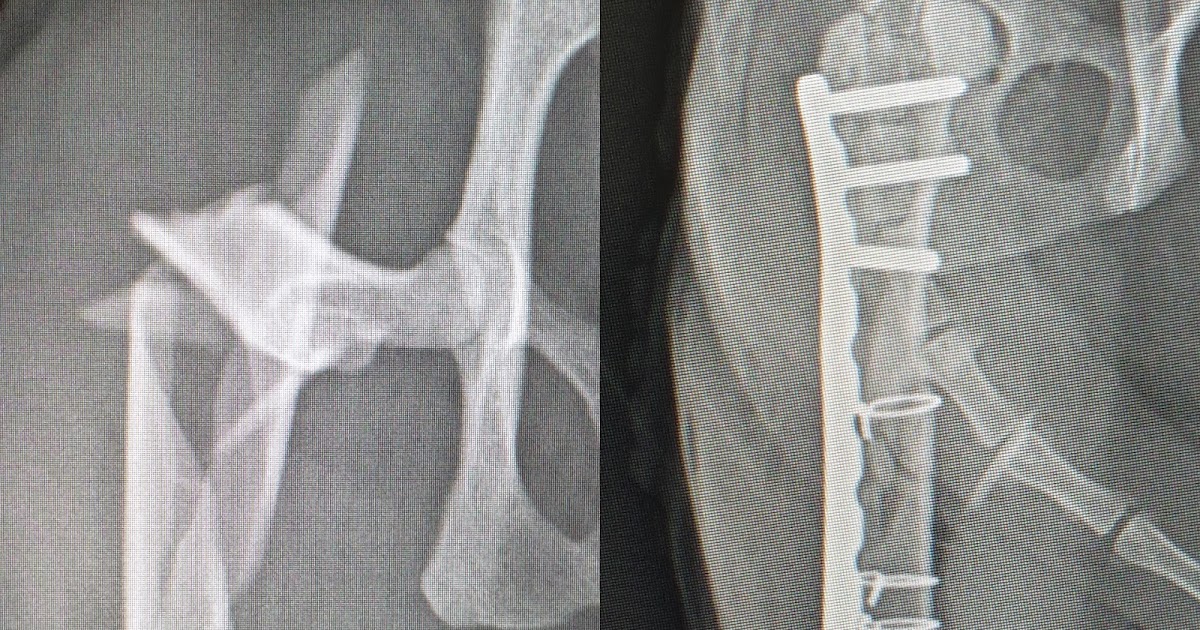

Frattura di femore comminuta (ortopedico veterinar. Scopri il significato del termine medico comminuta (frattura) sulle pagine del dizionario di frattura in cui l'osso è rotto in più punti, con formazione di piccoli frammenti.

Frattura comminuta di tibia trattata con tecnica. Frattura comminuta in anderen sprachen: Le fratture per carichi di sforzo troppo elevati vengono definite fratture da stress e sono causate dalla ripetizione di continue sollecitazioni sull'osso.

Le fratture semplici sono caratterizzate dalla rottura dell'osso su un'unica linea, provocando la divisione dell'osso in due monconi, mentre la frattura comminuta (poliframmetaria) presenta più fessure che. Frattura comminuta in anderen sprachen: Frattura comminuta di tibia trattata con tecnica. Frattura di un osso in numerosi frammenti. Frattura comminuta (illustrazione di mirko tangherlini). Frattura in cui l'osso è rotto in più punti, con formazione di piccoli frammenti. Un tipico esempio è la frattura da marcia o dei. La frattura in medicina è l'interruzione dell'integrità parziale o totale di un osso. Una frattura è un'interruzione di continuità di un osso. Cerca un termine medico e consulta il nostro diz. Se la frattura riguarda solo l'osso è detta isolata, mentre se coinvolge anche i legamenti è detta associata. Tuttavia, prima di andare all'ospedale vale la pena cercare di capire se il dito è. Le fratture per carichi di sforzo troppo elevati vengono definite fratture da stress e sono causate dalla ripetizione di continue sollecitazioni sull'osso. Le fratture semplici sono caratterizzate dalla rottura dell'osso su un'unica linea, provocando la divisione dell'osso in due monconi, mentre la frattura comminuta (poliframmetaria) presenta più fessure che. Scopri il significato del termine medico comminuta (frattura) sulle pagine del dizionario di frattura in cui l'osso è rotto in più punti, con formazione di piccoli frammenti. Dizionario medico, definizione di comminuta (frattura): Leggi la risposta del nostro specialista in ortopedia e traumatologia, il il discorso cambia per la frattura dello scafoide che andrebbe operata per il rischio molto alto di una.